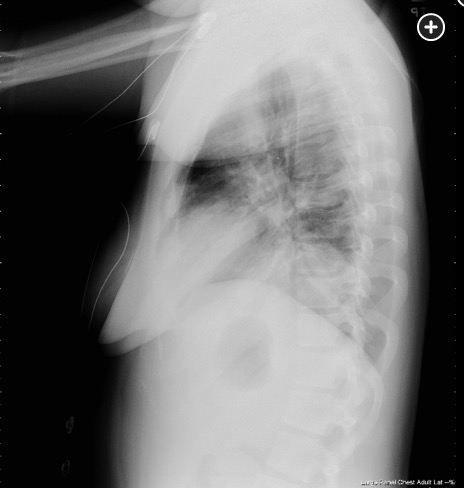

A 28-year-old woman with no known medical conditions presents to the ED with a 3-day history of fever, productive cough, and increasing shortness of breath. Prior to the onset of this illness she had experienced no other symptoms or signs, and there is no relevant epidemiological history related to her illness. On exam, she is acutely ill but is oriented to time, place, and person. Her temperature is 39.2°C, with a BP of 96/78 mm Hg, pulse of 122/min, and respirations of 34/min. Chest exam reveals diffuse crackles with consolidation findings over left lung base posteriorly. The remainder of her exam is unrevealing. Room air blood gases are a pH of 7.56, PCO2 of 29 mm Hg, and PO2 of 54 mm Hg. Her chest radiographs are shown in Figure 1 and Figure 2. Blood cultures drawn at the time of presentation are positive in 12 h for Streptococcus pneumoniae. Tests for HIV and influenza are negative. Based on this clinical presentation, what is the most likely finding that would explain the underlying basis for this patient’s clinical presentation of bacteremic pneumococcal pneumonia?

The underlying conditions for severe pneumococcal infection parallel the indications for pneumococcal vaccine: functional or anatomical asplenia, HIV infection, lymphoma (both Hodgkin and non-Hodgkin), and multiple myeloma. An additional risk factor for severe pneumococcal infection is alcohol use disorder. Analogous to herpes zoster infection (in which immunosuppression is a classic risk factor for the development of multidermatomal zoster), compromise of humoral immunity (as can occur with multiple myeloma and lymphoma) predisposes to the development of multilobar pneumococcal pneumonia. Given this patient’s severe clinical course with multilobar involvement, a search for an immunocompromising state would be prudent. Her age argues against multiple myeloma but in favor of lymphoma, which could result in a defect in her humoral immunity. The finding of intrathoracic lymphadenopathy, which was suspected based on the findings on her admission chest radiographs, would be consistent with such a diagnosis (choice A is correct).